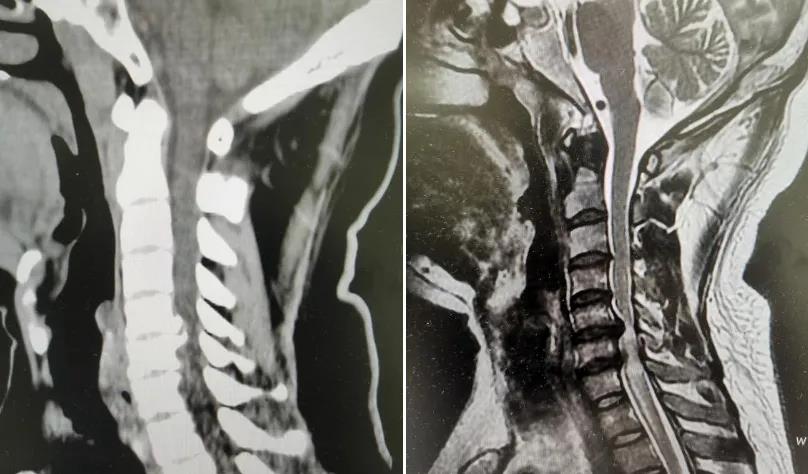

患者自述平日感觉颈肩部酸痛不适,伴有四肢麻木乏力、胸腹部束带感,以及行走不稳已有两个月,一直采取保守治疗,效果欠佳且病情有愈发加重的趋势。入院后脊柱微创团队为其系统检查,唐福兴博士认真研究病情,结合临床表现及影像学资料,明确诊断为“颈椎C5/6、C6/7脊髓型颈椎病”。其病理基础为C5/6、C6/7节段颈椎间盘突出,伴相应节段椎体后缘严重骨赘增生,导致颈脊髓严重受压、变性。循证医学证据认为,脊髓型颈椎病一旦确诊,即需尽早手术治疗。科主任王义生教授和科副主任刘昌生教授组织团队讨论后认为,患者已经出现脊髓损伤表现,随时有瘫痪加重风险,一致决定采用OSE内镜辅助下C5/6、C6/7椎间盘切除减压+零切迹融合器植骨融合内固定术。通俗点说,就是用内镜把颈椎里堵塞的地方清理干净,而又能最大限度的不伤及脊髓,再把它牢牢固定住,就像把隧道里的淤泥清掉,然后把隧道壁加固一样。

▲C5/6、C6/7节段颈椎间盘突出,伴相应节段椎体后缘严重骨赘增生,导致颈脊髓严重受压、变性(左:术前颈椎CT;右:术前颈椎MRI)